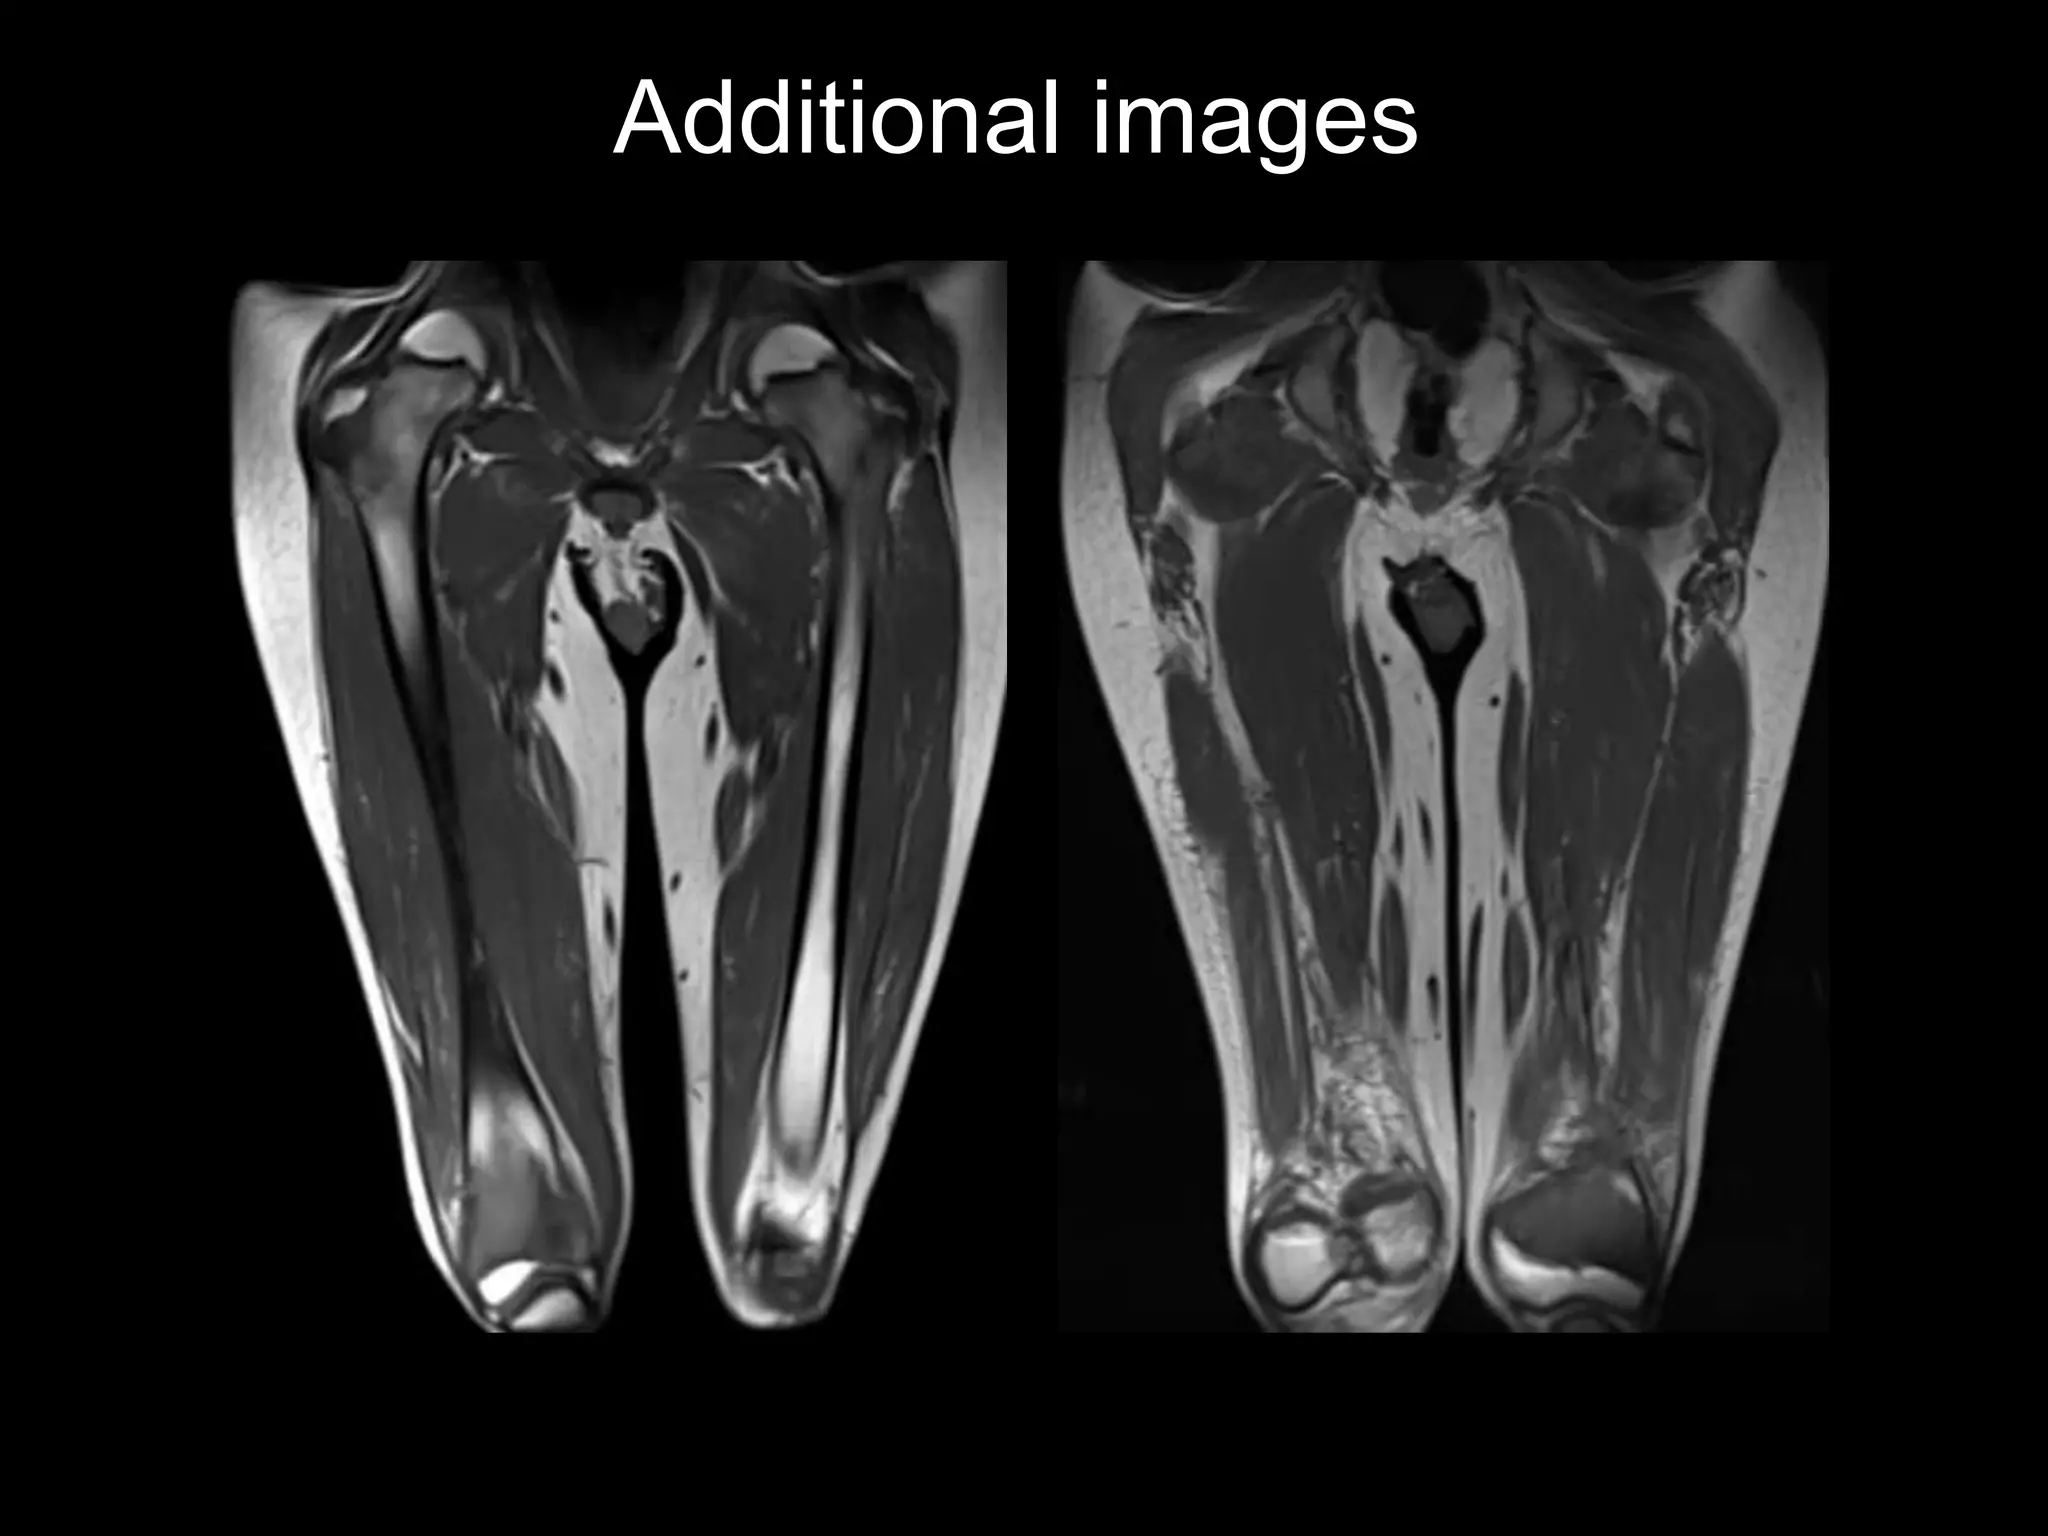

11 y.o. boy with 6 months of bilateral knee pain, right > left

Additional images

Findings

• Benign appearing tibial metaphyseal lesion

– Vascular (enhancement)

– No marrow edema or soft tissue mass

– Cortically based, sclerotic margins

• Systemic physeal widening

– Faint ZPC

– Metaphyseal fraying, osteopenia

Phosphaturic mesenchymal tumor

(PMT) with oncogenic osteomalacia

• Benign mesenchymal neoplasm

• Secretes phosphatonin (FGF 23)

– Inhibits renal phosphate reabsorption and conversion of

25-hydroxyvitamin D > 1,25 dihydroxyvitamin D

– Result is osteomalacia (rickets)- paraneoplastic

syndrome

• Tumor locations: extremities, facial bones

PMT with osteomalacia

• Labs

– low serum phosphate, normal

calcium

– high 25-hydroxyvitamin D, low

1,25 dihydroxyvitamin D

– elevated FGF 23

• Imaging: Whole Body MR for

occult lesions

• RX: surgical resection (FGF

levels normalize in 1wk)